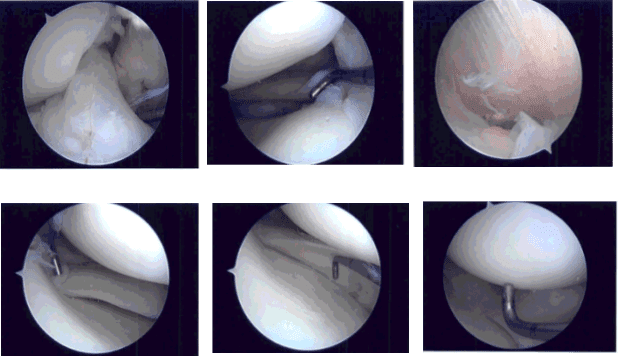

Se construyó un portal de entrada lateral y se accedió al artroscopio. El examen de la articulación patelofemoral no mostró daños. La canaleta medial mostraba escombros. El endoscopio se trasladó al compartimento tibiofemoral medial, donde se pudo ver una pequeña rotura en el cuerno posterior del menisco medial.

Se realizó un portal de acceso médico con el uso de una aguja espinal. Se entró en la sonda y se confirmaron las lágrimas. El desgarro se eliminó usando mordida ascendente y afeitadora. El resto del menisco estaba estable. El endoscopio se trasladó a la zona intercondilar donde el LCA estaba intacto.

El endoscopio se trasladó al compartimento tibiofemoral lateral. Había una pequeña rotura en el cuerno posterior del menisco lateral. El desgarro se eliminó con el uso de una afeitadora. El resto del menisco estaba intacto. No hubo movimiento excesivo del menisco.

El cartílago del cóndilo femoral medial y lateral permanecía intacto. El endoscopio de la rodilla se introdujo en la articulación patelofemoral. El examen de la tróclea y la superficie posterior de la rótula circular se encontró intacto. No se encontraron cambios artríticos. La rodilla fue completamente irrigada y drenada.

Foto intraoperatoria